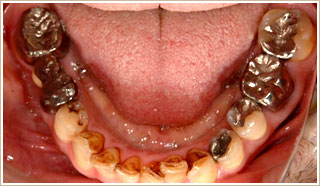

ケース2

約15年前に奥歯を抜いてから、下顎が喉の方に押し込まれていく感覚が発現。以後、数件の歯科医院で咬合治療を受けるが著明な効果がなかった。10ヶ月前から、某歯科医院でインプラント治療とクラウンの処置を受けるが、以下のような症状が改善せずに石井歯科医院に転院する。

前歯で咬みきれない、左でなんとか咀嚼できるが、右はうまく噛めない状況。前歯が強く当たるので削合して欲しい。

就眠中に下顎が後退する。頭痛。首が痛い。頭肩が重たい。顎がだるい。

▼治療前

治療前の写真を見ると、全体的に噛み合わせが高過ぎます。

当たっている歯と当たっていない歯の極端な高低差があります。

矢印の部は、上下の歯の距離が空いています。治療後は、噛み合わせの安定感が増したのが分かります。

治療過程

まず、歯を削合して高さを減じながら、歯と歯の高低差を無くして出来るだけ全体に咬合力を分散するようにします。

約3週間で咀嚼は出来るようになりました。

次に前歯及びクラウンのかぶせていない歯の位置を変えるため、歯列矯正を行います。

歯列矯正の期間は、7ヶ月でした。

詰めものやクラウンを入れ変えます。治療終了後の状態です。

1ヶ月に3,4回の受診で、全治療期間は15ヶ月でした。